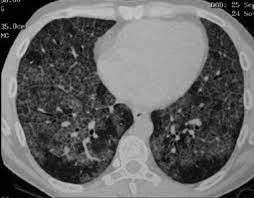

Hallazgos Radiológicos:

• Tomografía Computarizada de Alta Resolución (TCAR): Muestra opacidades reticulares y lineales, predominantemente en las bases y subpleurales, con cambios de «panal de abejas» (honeycombing). La distribución de la fibrosis es parcheada y no uniforme en el tiempo o el espacio. Las áreas normales de pulmón pueden estar adyacentes a áreas de fibrosis avanzada.

La tomografía computarizada de alta resolución (TCAR) proporciona información crucial para el diagnóstico. En la FPI, la TCAR muestra un patrón característico con opacidades predominantes en las bases y en los bordes periféricos de los pulmones. También se observan bronquiectasias por tracción y cambios tipo panal de abejas, que indican la presencia de fibrosis avanzada. La combinación de estos hallazgos permite a los médicos confirmar el diagnóstico sin necesidad de una biopsia pulmonar en la mayoría de los casos.